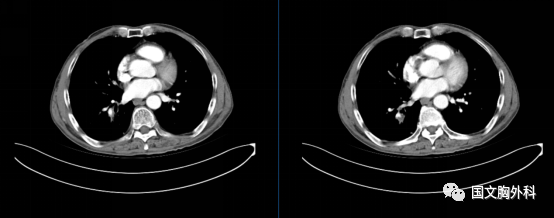

入院時胸部CT,提示:胸部CT平掃+增強:右肺下葉占位,符合肺癌表現(xiàn),伴周圍阻塞性肺炎??v隔、右肺門稍大淋巴結(jié),轉(zhuǎn)移不除外。

治療前 ↓

治療后↓